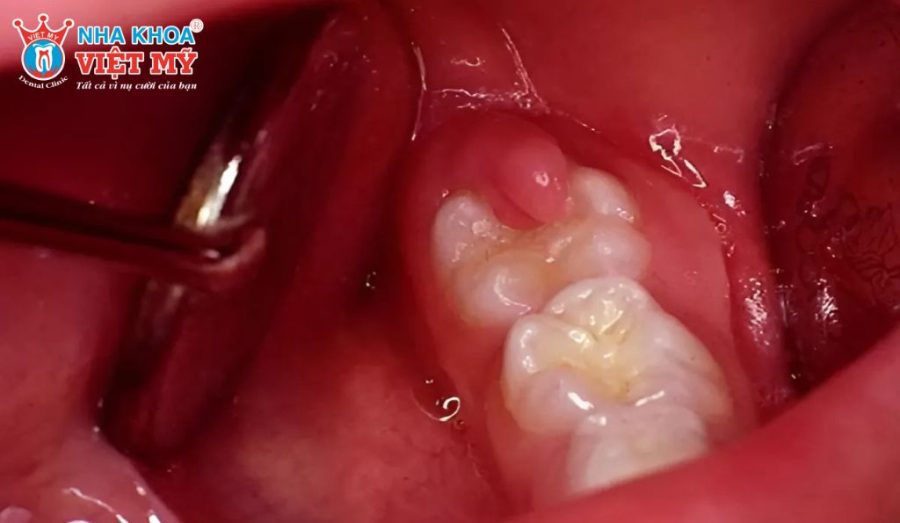

Do vị trí răng phức tạp, khó tiếp cận

Những trường hợp răng khôn mọc lệch, mọc ngầm hoặc răng nằm sâu trong xương hàm thường khó nhổ hơn. Quá trình phẫu thuật phức tạp có thể làm tổn thương mô mềm và xương, tạo điều kiện cho vi khuẩn phát triển.

Khám lâm sàng

Bác sĩ sẽ quan sát trực tiếp vùng răng vừa nhổ, kiểm tra tình trạng sưng, đỏ, đau, có mủ hoặc mùi hôi bất thường. Đồng thời, bệnh nhân sẽ được hỏi về triệu chứng như chảy máu kéo dài, sốt hay khó mở miệng. Đây là bước đầu tiên và quan trọng nhất để định hướng nguyên nhân.